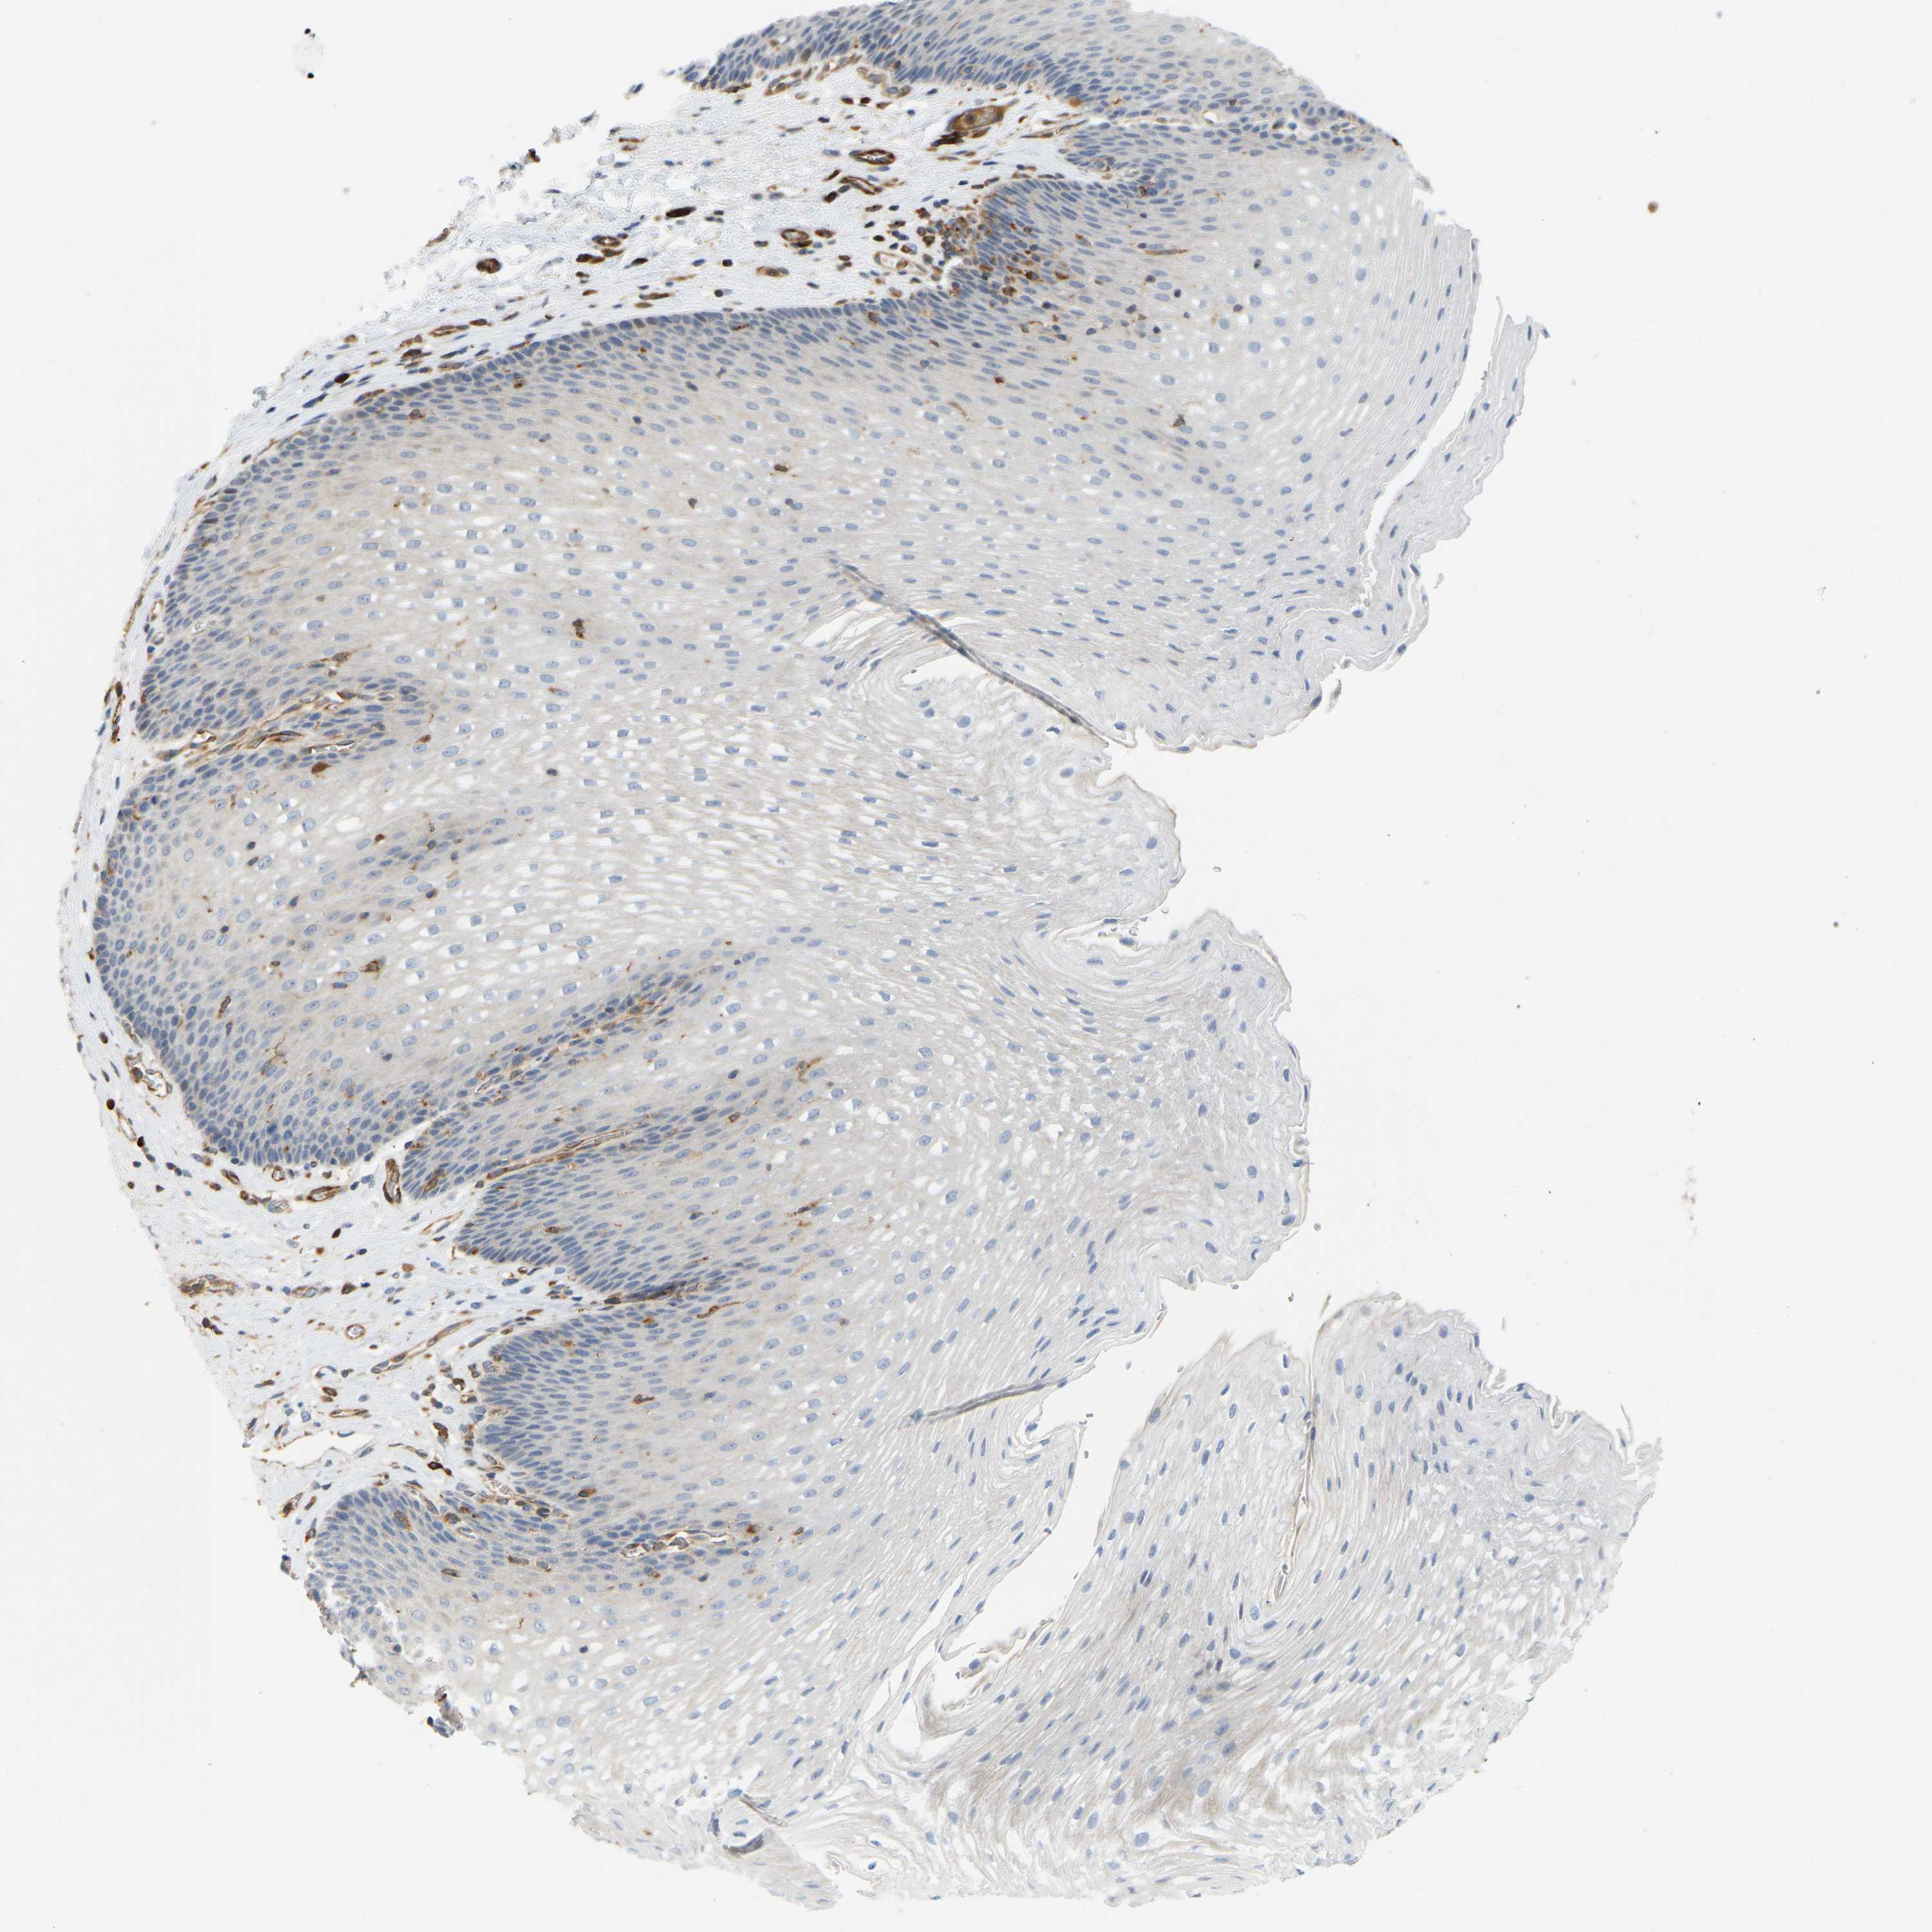

ESOPHAGUS - Antibody stainingi

Antibody staining in the annotated cell types in the current human tissue is reported as not detected, low, medium, or high, based on conventional immunohistochemistry profiling in selected tissues. This score is based on the combination of the staining intensity and fraction of stained cells.

Each image is clickable and will lead to virtual microscopy that enables deeper exploration of all samples and also displays staining intensity scores, fraction scores and subcellular localization as well as patient and tissue information for each sample.

Antibody HPA020099Antibody HPA020100Antibody CAB004280

Squamous epithelial cells Not detectedNot detectedLow